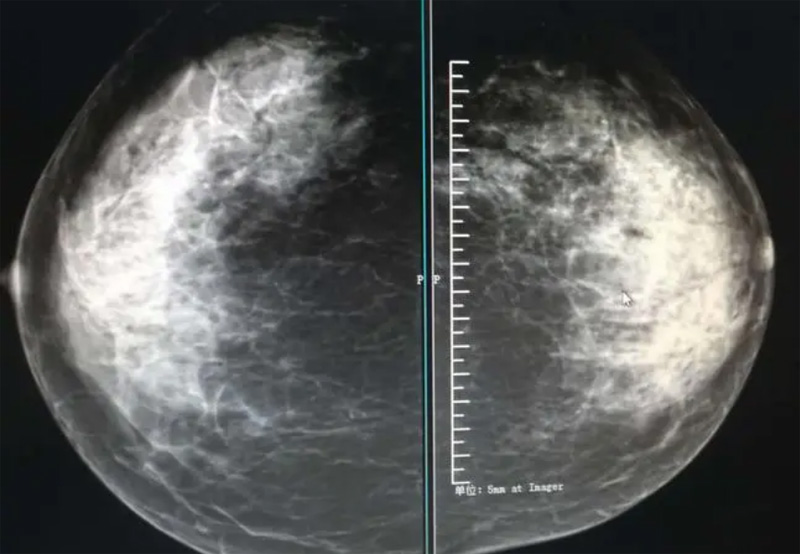

乳腺DR攝影體位有頭尾位及內(nèi)外側(cè)斜位,

乳房在片子的中央,乳頭切線位,可見(jiàn)小部分胸大肌,內(nèi)側(cè)乳腺組織應(yīng)全部包括在片中,外側(cè)乳腺組織盡可能包括在片中。一張好的MLO位圖像顯示如下:乳房被推向前上,乳腺實(shí)質(zhì)充分展開(kāi),胸大肌可見(jiàn),較松弛,下緣達(dá)到乳頭水平,乳頭在切線位,部分腹壁包括在片中,但與下部乳腺分開(kāi),絕大部分乳腺實(shí)質(zhì)顯示在片中。乳腺組織外緣可見(jiàn)乳頭的輪廓;乳腺后方的脂肪組織被很好地顯示出來(lái),乳房無(wú)皺褶。對(duì)于CC位及MLO位顯示不良或未包全的乳腺實(shí)質(zhì),可以根據(jù)病灶位置的不同選擇以下體位:外內(nèi)側(cè)位(LM)、內(nèi)外側(cè)位(ML)、內(nèi)側(cè)頭尾軸位(MCC)、外側(cè)頭尾軸位(LCC),尾葉位(CLEO)及乳溝位。在臨床實(shí)踐中,對(duì)于常規(guī)體位上發(fā)現(xiàn)的異常改變,可以進(jìn)一步采取一些特殊的攝影技術(shù),包括局部加壓攝影、放大攝影或局部加壓放大攝影技術(shù)。

2、規(guī)范觀圖程序:屏幕軟閱讀或在專用日光觀片燈下膠片閱讀,后者應(yīng)同時(shí)準(zhǔn)備白熾強(qiáng)光燈及觀片放大鏡。注意雙側(cè)乳腺配對(duì)觀察,推薦雙眼橫向掃描,進(jìn)行雙乳相同部位圖像比較分析。

3、乳腺實(shí)質(zhì)背景的確定:觀察乳腺實(shí)質(zhì)與脂肪的構(gòu)成比例,了解乳腺實(shí)質(zhì)類型,以判斷對(duì)某些乳腺攝影征象敏感性的影響,有利于確定乳腺攝影對(duì)疾病的診斷價(jià)值。

必須指出的是,美國(guó)放射學(xué)會(huì)提出的乳腺影像報(bào)告和數(shù)據(jù)系統(tǒng)(Breast Imaging Reporting and Data System, BI-RADS)將乳腺分為4型:脂肪型(乳腺內(nèi)幾乎全部為脂肪組織,腺體組織占25%以下)、少量腺體型(乳腺內(nèi)散在腺體組織,大約占25%~50%)、多量腺體型(乳腺呈不均勻致密表現(xiàn),腺體組織大約占51%~75%)、致密型(乳腺組織非常致密,腺體組織占75%以上)。這種分型的主要意義在于說(shuō)明X線對(duì)不同乳腺類型中病變檢出的敏感性不同,對(duì)發(fā)生在脂肪型乳腺中病變的檢出率很高,而對(duì)發(fā)生在致密型乳腺中病變的檢出率則有所降低,臨床醫(yī)師了解這一點(diǎn)很重要。